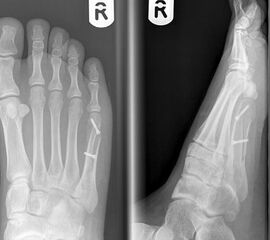

Abb. 3a, b: Präoperatives (a) und postoperatives (b) Röntgenbild bei Korrektur einer Typ I Deformität durch eine Exostosenabtragung.